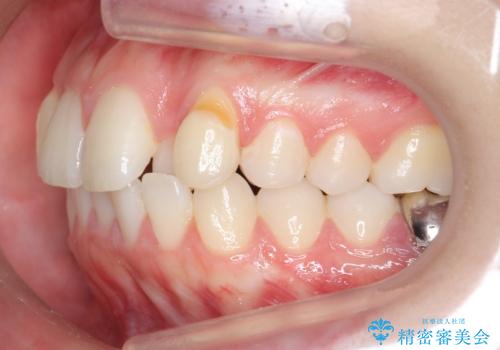

- 前歯のがたつきを主訴に来院。

左上の犬歯が歯肉退縮しており、そこを抜歯して矯正することにしました。

右上については、奥歯をインプラント矯正により後ろに動かして、引っ込んだ前歯を並べるスペースを確保しました。

右下6番については保存不可能であり、矯正治療終了後にインプラント補綴しています。